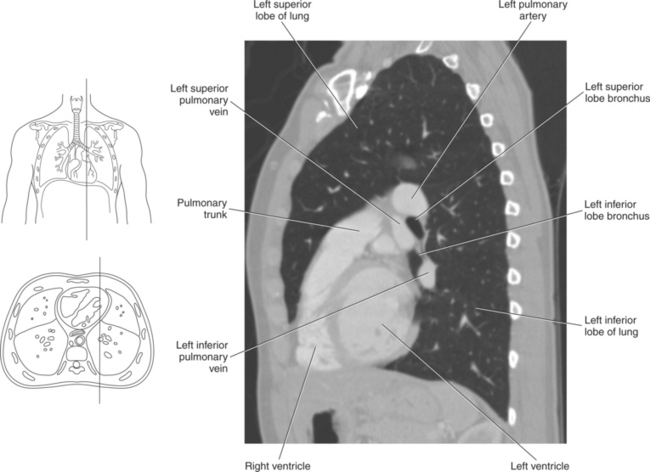

Blood travels to and from the heart through the great vessels, which include the aorta, pulmonary arteries and veins, and superior and inferior venae cavae (Figures 6.54 and 6.55). The aorta is the largest artery of the body and can be divided into the ascending aorta, aortic arch, and descending aorta. The ascending aorta begins at the base of the left ventricle at the level of the sternal angle, then curves superiorly and posteriorly as the aortic arch over the root of the left lung. The top of the aortic arch is approximately at T3 (Figures 6.56 and 6.57). The arch continues as the descending aorta posterior to the left bronchus and pulmonary trunk, on the left side of the vertebral body of T4 (Figures 6.58 and 6.59). The descending aorta passes slightly anterior and to the left of the vertebral column as it descends through the thoracic and abdominal cavities (Figure 6.60). While in the thoracic cavity, the descending aorta is commonly called the thoracic aorta, and while in the abdominal cavity, it is called the abdominal aorta. The pulmonary trunk is the origin of the right and left pulmonary arteries and lies entirely within the pericardial sac. It arises from the right ventricle and ascends in front of the ascending aorta, courses posteriorly and to the left, where it bifurcates at the level of the sternal angle (T4) into the right and left pulmonary arteries (Figures 6.61 through 6.63). The pulmonary trunk is attached to the aortic arch by a fibrous cord called the ligamentum arteriosum, the remnant of an important fetal blood vessel (ductus arteriosus) that links the pulmonary and systemic circuits during fetal development (Figures 6.54 and 6.61). The right pulmonary artery courses laterally, posterior to the ascending aorta and superior vena cava, and anterior to the esophagus and right mainstem bronchus, to the hilum of the right lung. At the root of the right lung, the right pulmonary artery divides into two branches, with the lower branch supplying the middle and inferior lobes and the upper branch supplying the superior lobe (Figures 6.61 through 6.64). The left pulmonary artery, shorter and smaller than the right, is also the most superior of the pulmonary vessels. It travels horizontally, arching over the left mainstem bronchus, and enters the hilum of the left lung just superior to the left mainstem bronchus (Figures 6.61 through 6.64). Within the lungs, each pulmonary artery descends posterolateral to the main bronchus and divides into lobar and segmental arteries, continuing to branch out and to follow along with the smallest divisions of the bronchial tree (Figures 6.61 and 6.64). Located inferior to the pulmonary arteries are the four pulmonary veins, two each (superior and inferior) extending from each lung to enter the left atrium (Figures 6.54, 6.55, 6.61, and 6.64 through 6.68). They commence in a capillary network along the walls of the alveoli, where they are continuous with the capillaries of the pulmonary arteries. The venous capillaries merge to form small vessels that unite successively to eventually form a single trunk for each lobe: three for the right and two for the left lung. Frequently the trunk from the middle lobe of the right lung unites with the trunk from the upper lobe, forming just two trunks on the right side prior to entering the left atrium. The right superior pulmonary vein collects blood from the upper lobe segments of the right lung and passes anterior and inferior to the right pulmonary artery, behind the superior vena cava. The right inferior pulmonary vein receives blood from the right lower lobes of the lung and crosses behind the right atrium to the left atrium (Figures 6.61 and 6.69 through 6.71). The left superior pulmonary vein receives blood from the left upper lobe of the left lung and courses anterior and inferior to the left main bronchus as it enters the left atrium. The left inferior pulmonary vein drains the inferior lobe of the left lung and passes toward the left atrium anterior to the bronchi (Figures 6.61 and 6.72 through 6.74). The pulmonary veins course more horizontally than the pulmonary arteries and are ultimately oriented toward the left atrium. At the root of the lungs, the pulmonary veins are anterior to the pulmonary arteries, which are anterior to the bronchus. While within the lungs, the branches of the pulmonary arteries are anterior to the bronchi, which are anterior to the pulmonary veins. The superior and inferior venae cavae are the largest veins of the body. The superior vena cava is formed by the junction of the brachiocephalic veins, posterior to the right first costal cartilage, and carries blood from the thorax, upper limbs, head, and neck (Figure 6.24). As it travels inferiorly, it is located posterior and lateral to the ascending aorta before entering the upper portion of the right atrium (Figures 6.54 through 6.59). The inferior vena cava is formed by the junction of the common iliac veins in the pelvis and ascends the abdomen to the right of the abdominal aorta and anterior to the vertebral column. It passes through the caval hiatus of the diaphragm and almost immediately enters the inferior portion of the right atrium (Figures 6.75 and 6.76).